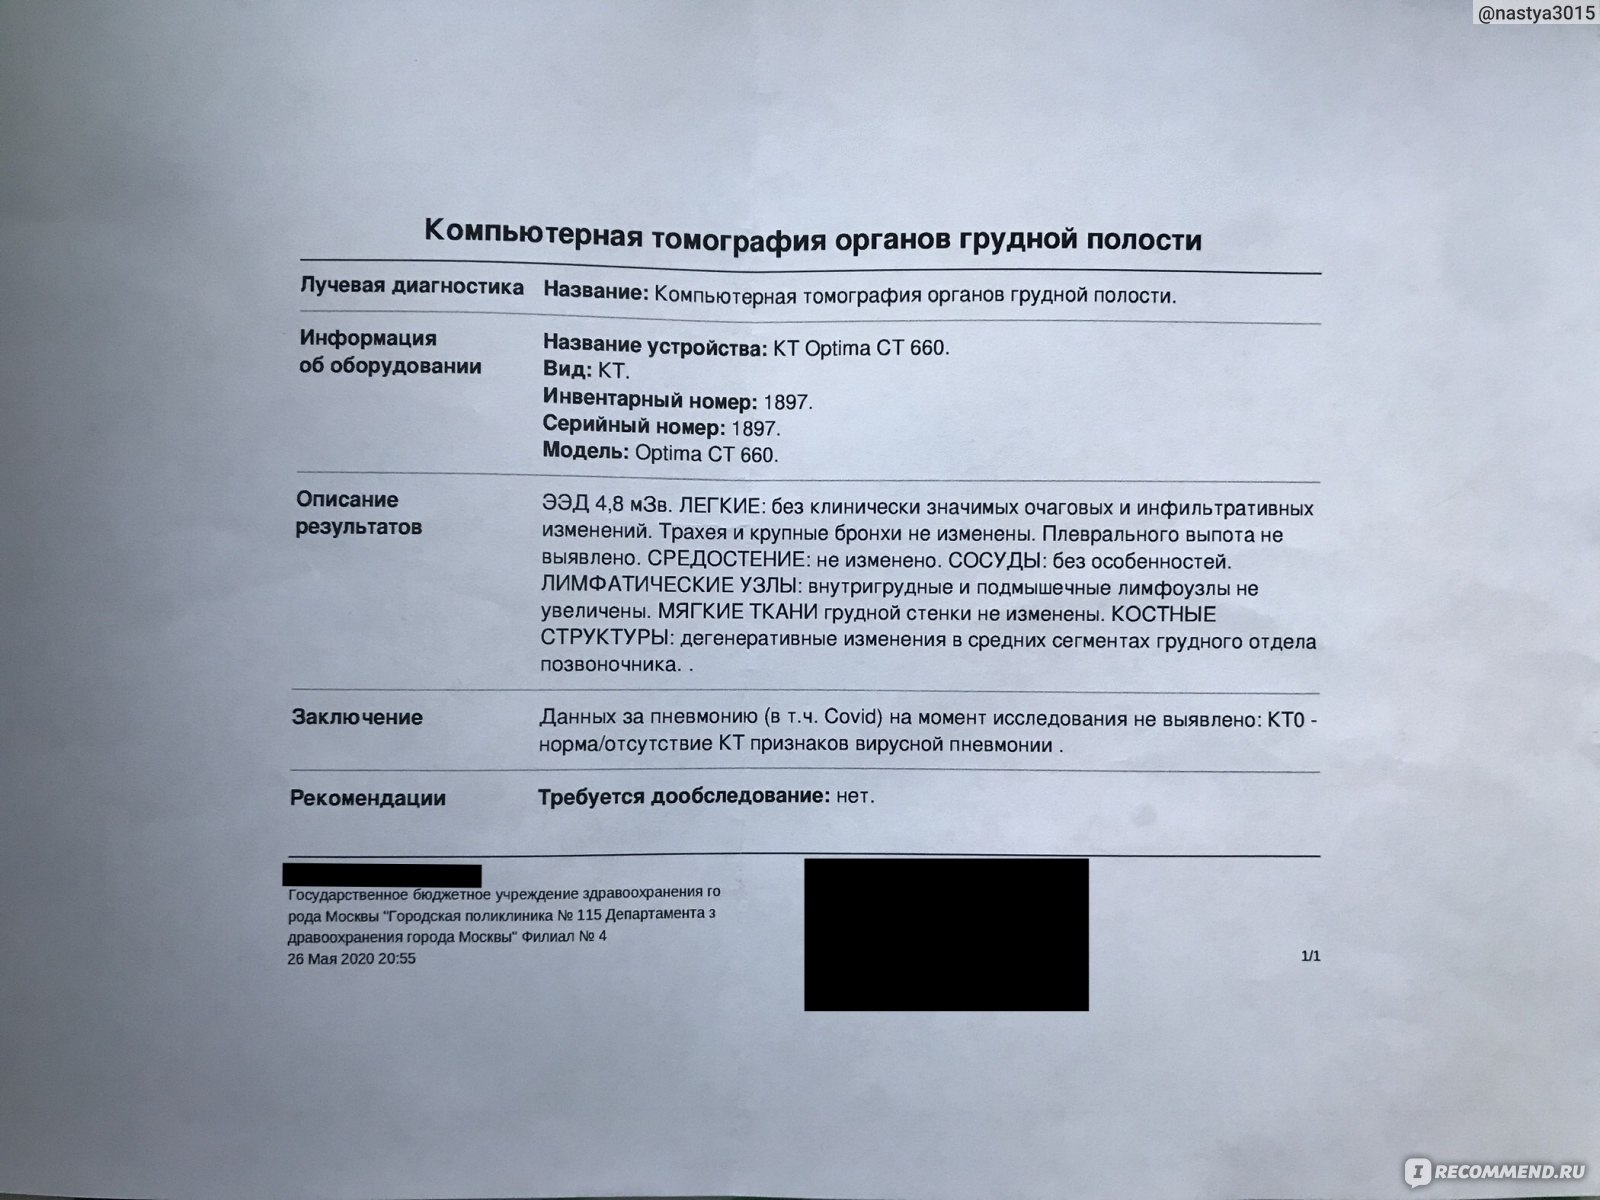

Фотографии и снимки КТ легких без контрастных веществ

Раздел: Визуальный дайджест